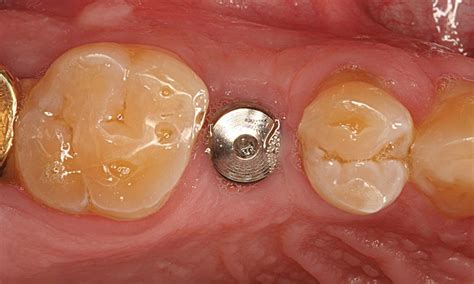

Dentro de este contexto, los tapones de cicatrización juegan un papel fundamental. Son críticos para la preparación de los tejidos para el momento de la colocación de las prótesis, conformando el tejido blanco que rodea el implante. Este elemento es una parte esencial de los implantes dentales, y pueden determinar el éxito del tratamiento.

Los tapones de cicatrización son componentes temporales colocados sobre los implantes dentales durante el proceso de curación. El pilar de cicatrización (también conocido como pilar gingival) es una pequeña pieza fabricada generalmente en titanio, aunque también puede elaborarse con materiales cerámicos o biocompatibles.

Además, los tapones de cicatrización se clasifican en:

- Tapones de cicatrización estándares: Son los más comunes y se utilizan en una amplia variedad de casos.

- Tapones de cicatrización anatómicos: Estos tapones están diseñados para adaptarse más específicamente a la anatomía individual del paciente. Imitan la forma natural del diente y la encía, ofreciendo una adaptación más precisa y un resultado estético superior.

- Cuidado de la zona: Durante 2 días debes comer liquido/blando y frío. Debes lavar tus dientes después de cada comida, los primeros días no cepilles la zona de la intervención. Debes aplicar gel de Clorhexidina sobre el tapón de cicatrización y sobre los puntos de sutura (si los llevas).